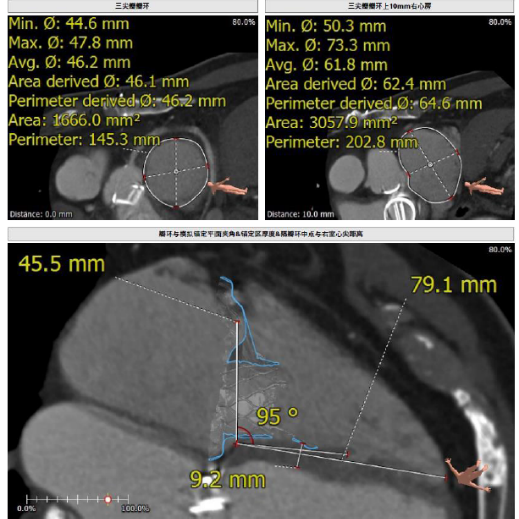

接受本次治療的是一例三尖瓣重度反流的患者,NYHA心功能Ⅲ級。主訴“反復(fù)活動后氣促1年,下肢水腫4個月”。入院N末端B型腦鈉肽前體(NT-proBNP)3161pg/ml。心電圖提示:心房顫動,ST-T改變。術(shù)前超聲提示:重度三尖瓣關(guān)閉不全,右心房擴大,三尖瓣收縮期位移(TAPSE)14mm,左房增大,左室收縮功能正常低值,主動脈瓣、二尖瓣機械瓣功能良好。術(shù)前CT評估(圖1):三尖瓣瓣環(huán)(周長換算直徑)大小為46.2mm;入路血管無嚴(yán)重迂曲,無鈣化;雙側(cè)冠脈有鈣化。